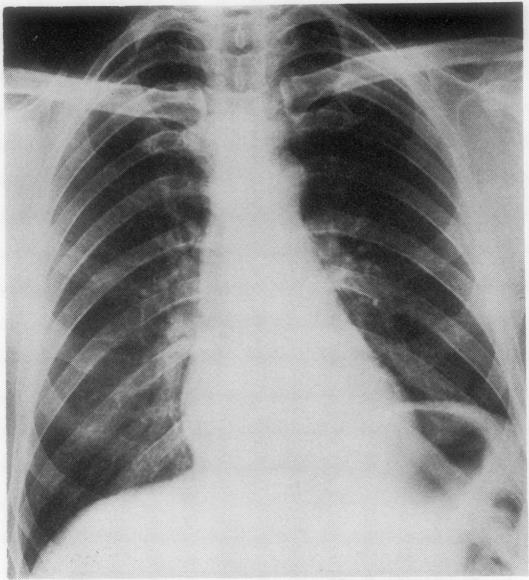

Spontaneous pneumopericardium is a relatively rare event, although cases have been recorded over the past 130 years. Many were associated with malignancy, trauma, infection or as a complication of recent surgery. Attempts at surgical resolution have been infrequent and survival extremely rare. We describe a patient in whom pneumopericardium developed spontaneously and insidiously, probably being present for some weeks before hospital investigation. Surgical exploration revealed the cause to be a benign gastric ulcer without an hiatus hernia or other diaphragmatic defect. Repair was attempted but the patient died in the early postoperative period. From an extensive review of the literature it is clear that spontaneous perforation of a gastric ulcer into the pericardium must be less rare than some authors have suggested.

自发性心包积气是一种相对罕见的情况,尽管在过去130年里已有病例记录。许多病例与恶性肿瘤、创伤、感染有关,或作为近期手术的并发症。手术解决的尝试并不常见,存活率极低。我们描述了一名患者,其心包积气是自发且隐匿性发生的,在医院检查前可能已经存在数周。手术探查发现病因是一个良性胃溃疡,没有食管裂孔疝或其他膈肌缺损。尝试进行了修复,但患者在术后早期死亡。通过对大量文献的广泛回顾,很明显胃溃疡自发穿孔进入心包的情况肯定不像一些作者所认为的那么罕见。